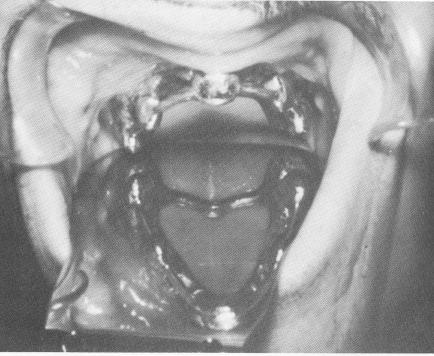

Fig. 10-225. The template was held in position while the pins were individually driven through the holes.

Fig. 10-226. The pins were secured to the template and the template was secured to the fibromucosal tissue by fastening the pins with cold cure acrylic.